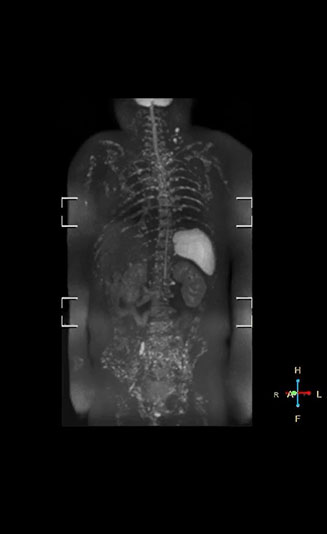

“When we limited the scan coverage to the area from neck to femur, we could fit more clinical information in approximately the same scan time. So, we added coronal mDIXON, sagittal T1-weighted, and sagittal STIR sequences to our examination, instead of performing only axial DWIBS and coronal single-shot TSE scans.” The single shot T2-weighted TSE images are used for morphology and compared to DWIBS images to identify T2 shine-through. Sagittal STIR images are used in patients with inflammation or bone metastasis.

“Switching to coronal DWIBS – rather than axial – further shortens scan time,” says Mr. Naka. “Important is that a dS SENSE factor of 5 shortens exam time while high image quality can be maintained, thanks to Ingenia’s dStream architecture.” He adds that the coronal orientation also avoids artifacts that are specific to combining axial images.

“When we use a coronal DWIBS acquisition, we can perform a full whole body examination, including other required sequences, within 30 minutes,” he says.